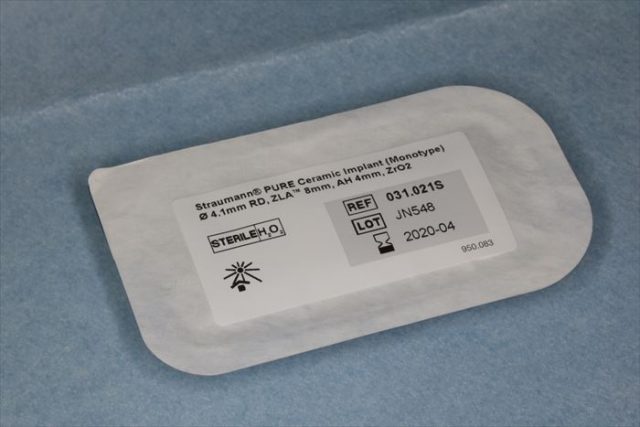

ストローマン ピュア セラミック インプラントを用意します。

挿入ジグをスナップフィットさせ、ジルコニアインプラントをピックアップします。